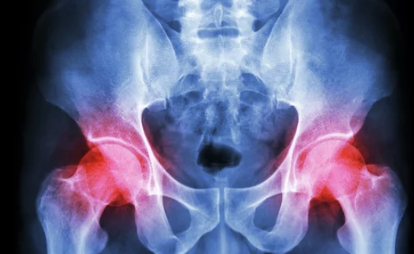

2. 고관절 통증, 왜 생기는 걸까? 주요 원인 심층 분석

고관절 통증은 다양한 원인에 의해 발생할 수 있습니다.

- 퇴행성 관절염: 나이가 들면서 연골이 닳아 발생하는 가장 흔한 원인입니다. 초기에는 뻐근함이나 불편함 정도지만, 심해지면 움직일 때마다 극심한 통증을 느낄 수 있습니다.

- 류마티스 관절염: 면역 체계 이상으로 발생하는 만성 염증 질환으로, 고관절을 포함한 여러 관절에 염증을 일으켜 통증과 강직을 유발합니다.

- 대퇴골두 무혈성 괴사: 혈액 공급이 차단되어 뼈 조직이 괴사하는 질환으로, 초기에는 특별한 증상이 없지만, 진행되면 갑작스러운 통증과 함께 보행 장애를 일으킬 수 있습니다.

- 고관절 충돌 증후군: 뼈의 비정상적인 형태로 인해 관절이 부딪히면서 통증이 발생합니다. 특히 젊은 층이나 운동선수에게서 자주 발생하며, 활동 시 뚝뚝 소리가 나거나 걸을 때 불편함을 느낄 수 있습니다.

정확한 원인을 파악하기 위해서는 병원을 방문하여 전문의의 진료와 정밀 검사(X-ray, MRI, CT 등)를 받는 것이 중요합니다.